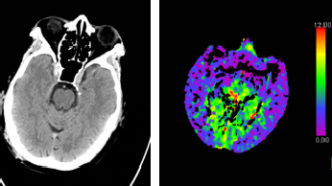

腦部CT檢查即電子計(jì)算機(jī)斷層掃描(Computed Tomography),是一種無(wú)創(chuàng)性檢查方法,通過(guò)X線和計(jì)算機(jī)技術(shù)相結(jié)合,獲取腦部結(jié)構(gòu)的橫斷面圖像,這種檢查方法可以清晰地顯示顱內(nèi)結(jié)構(gòu),對(duì)于診斷腦出血、腦梗塞、腦腫瘤等疾病具有重要意義。

2、局限性:雖然腦部CT檢查具有較高的診斷價(jià)值,但也存在一定的局限性,對(duì)于某些疾病,如早期腦梗塞、輕微腦震蕩等,CT檢查可能無(wú)法準(zhǔn)確診斷,腦部CT檢查主要關(guān)注結(jié)構(gòu)異常,對(duì)于某些功能性問(wèn)題,如認(rèn)知障礙、情緒問(wèn)題等,無(wú)法直接判斷。

2、其他檢查方法:除了腦部CT檢查外,還有其他檢查方法,如腦電圖(EEG)、磁共振成像(MRI)等,可以輔助診斷腦部疾病,這些檢查方法可以檢測(cè)腦部功能異常和某些細(xì)微結(jié)構(gòu)變化。